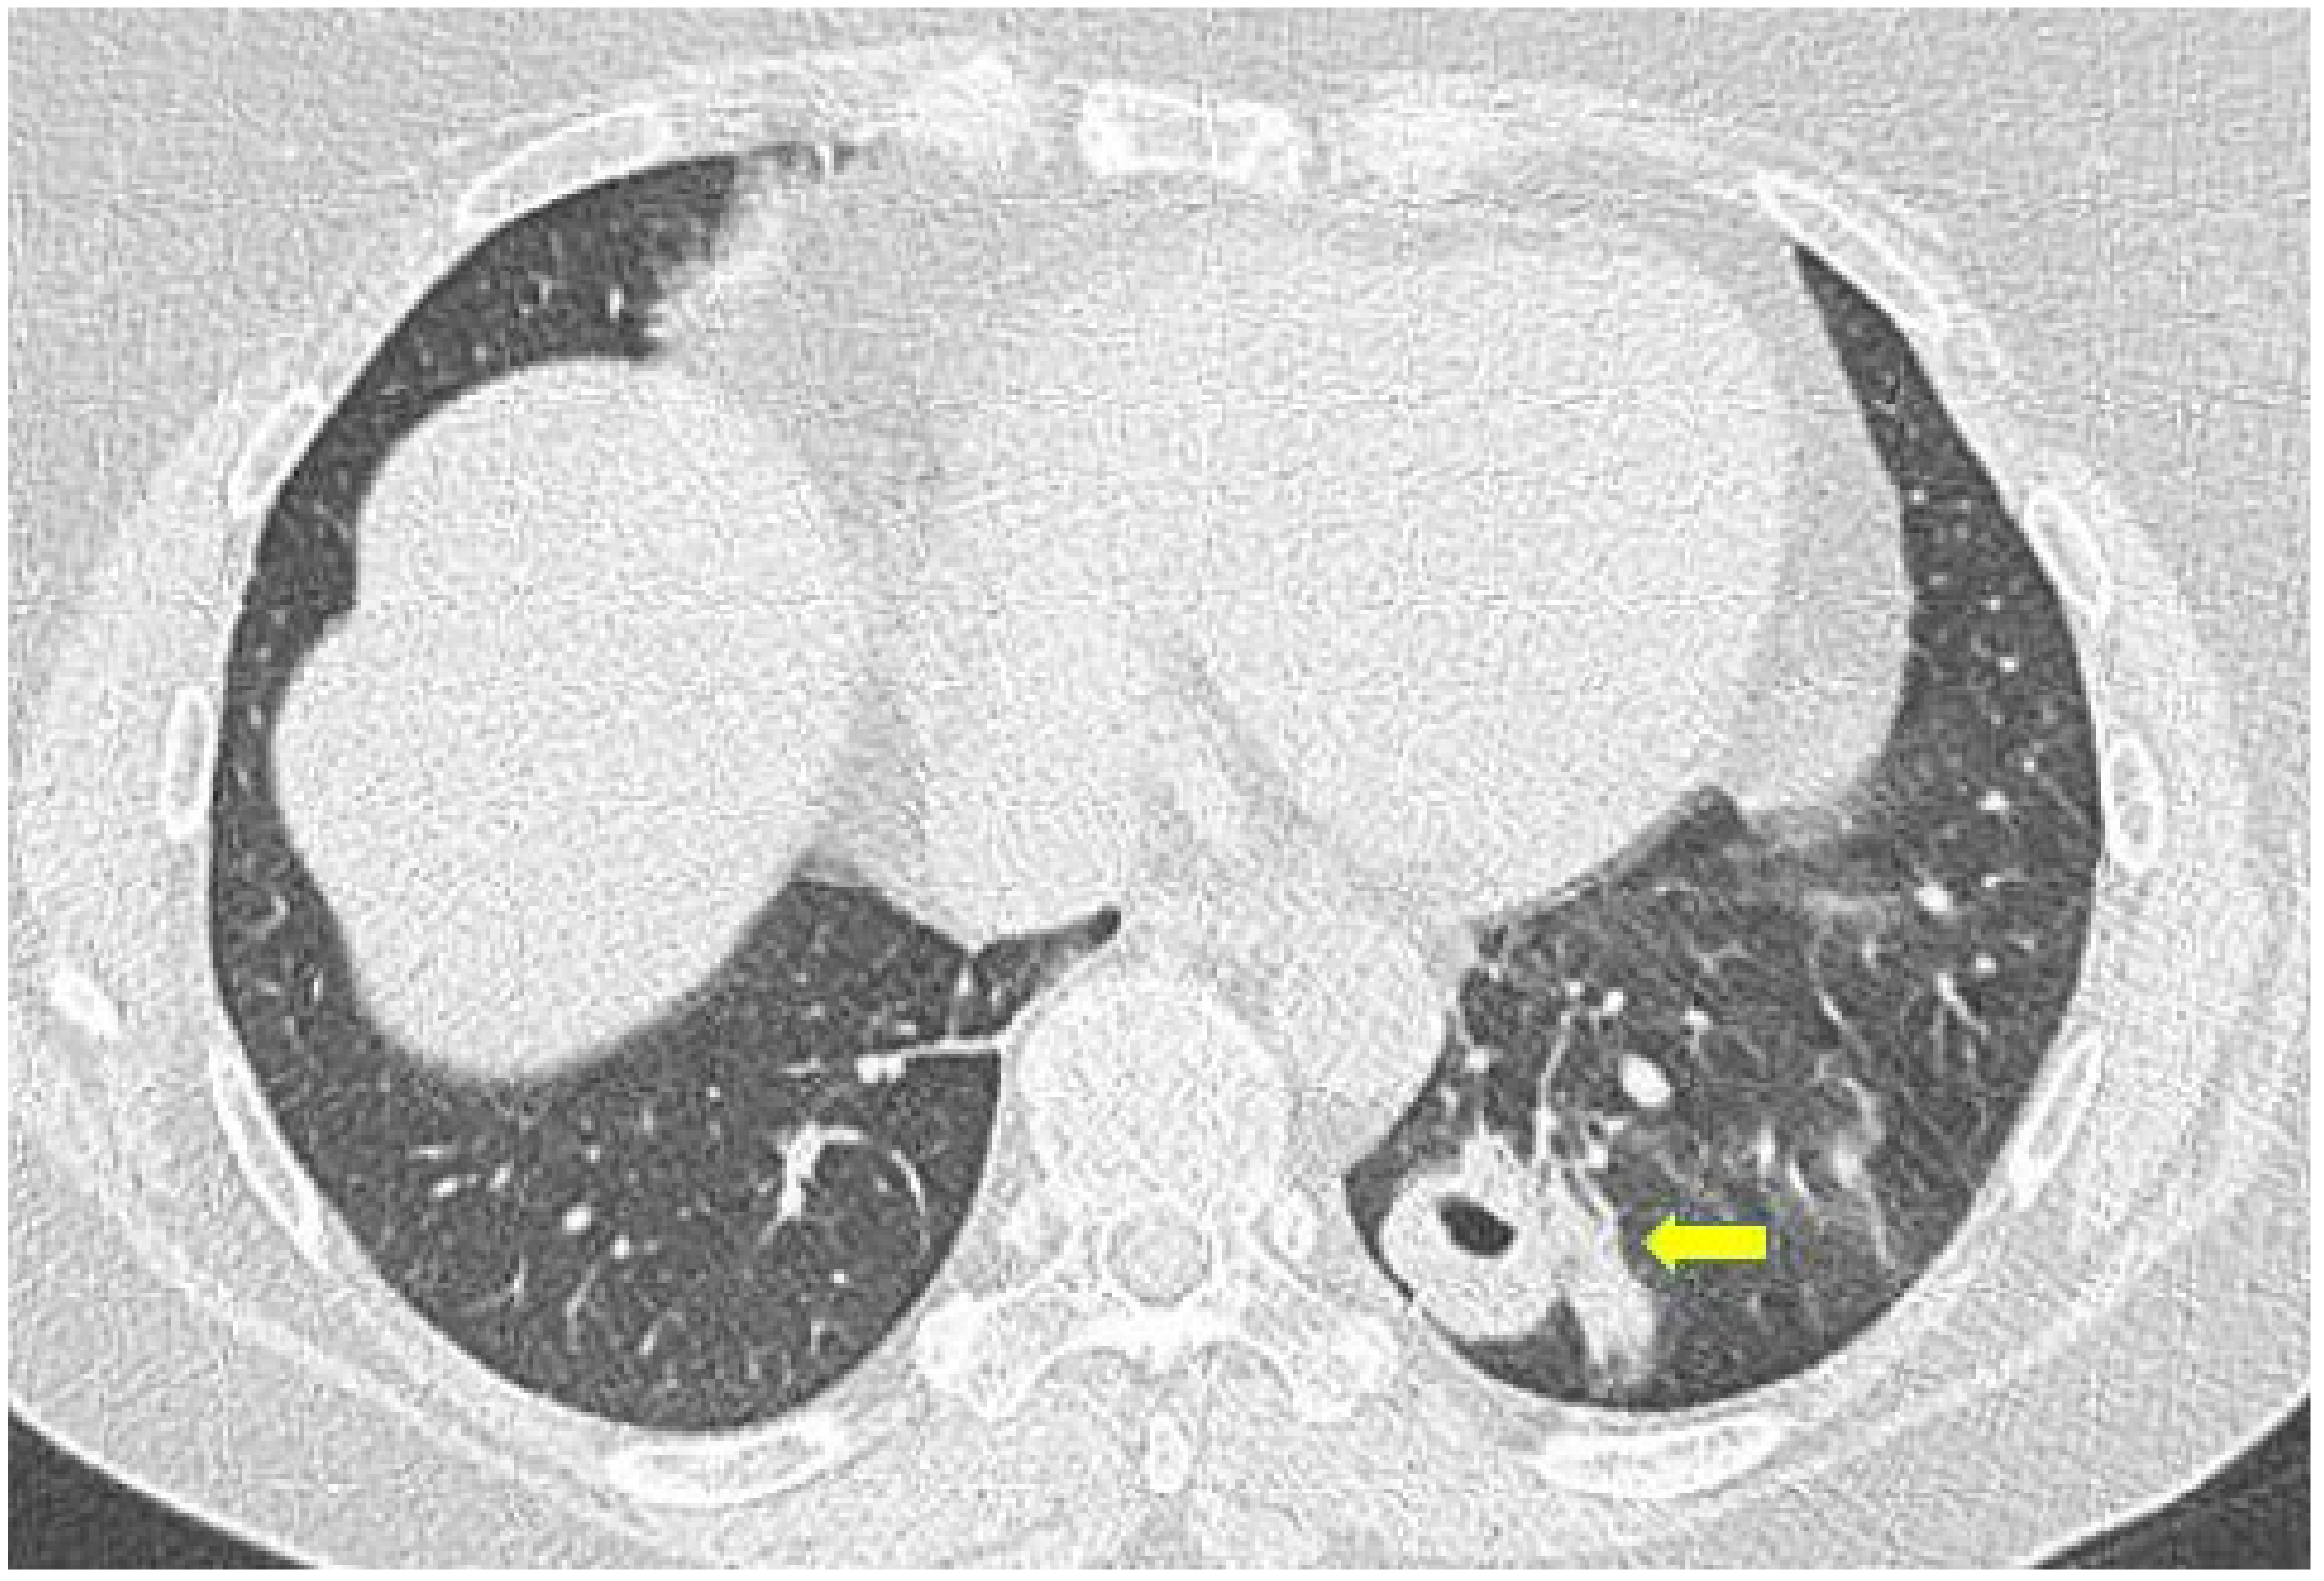

2.3. Microscopic Polyangiitis (MPA)

| MPA | GGOs due to hemorrhagic alveolitis (common); consolidation, nodules with centrilobular distribution (less common) |